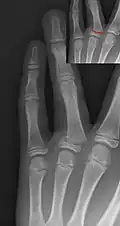

Salter–Harris III fracture of big toe proximal phalanx. -

Salter–Harris IV fracture of big toe proximal phalanx.